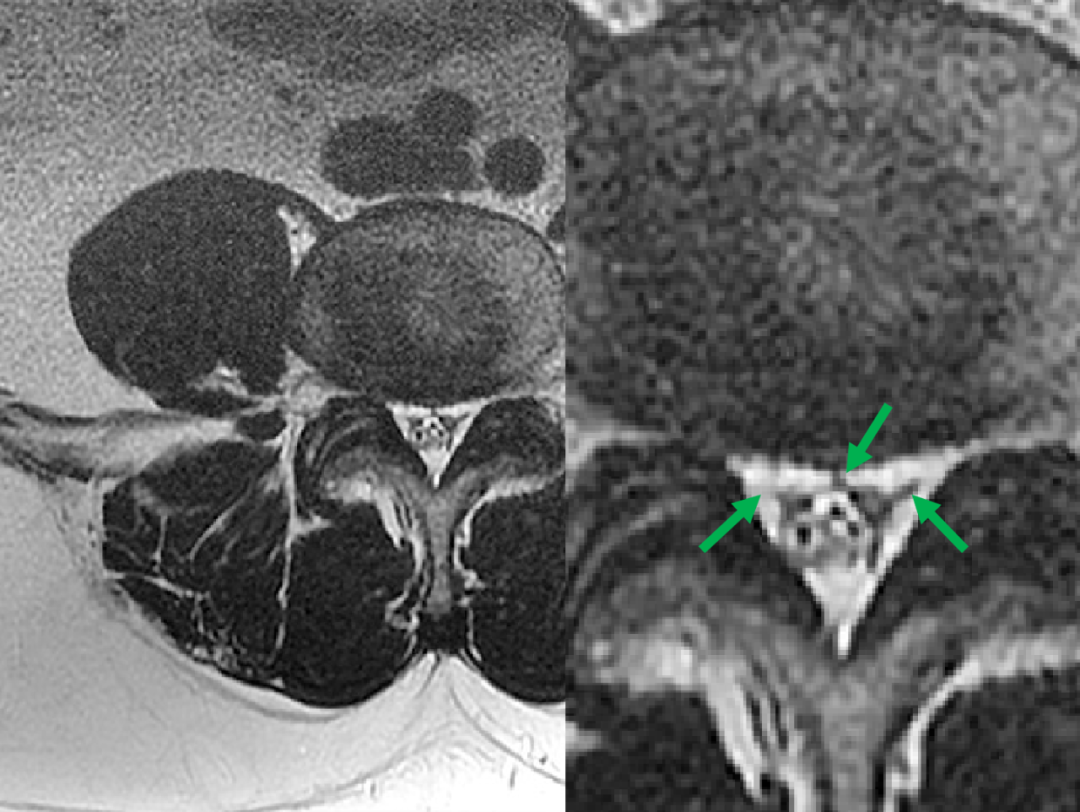

一例长期使用激素治疗的儿童,椎管内硬膜外脂肪明显增多,背侧脂肪前缘超过椎板前缘,脊髓受压呈 「 圆饼 」 状。

轴面上 T2WI 收到硬膜外脂肪的推挤,硬膜囊可以发生变形(正常为椭圆形)通常为多边形(A)、星状(B)或 Y 形或 V 形(C-D)

腰椎管横切面显示:硬膜外间隙存在硬脊膜椎韧带,正中(A 中的箭头)、双侧旁正中(B 中的箭头)和外侧(C 中的箭头),向后牵拉硬膜囊(S:塌陷的硬膜囊)

硬脊膜椎韧带向前牵拉硬膜囊(S:塌陷的硬膜囊)

硬脊膜椎韧带的分布也存在变异,数字代表在各个方向出现的频率

那么绿箭头所示的其实是硬脊膜椎韧带